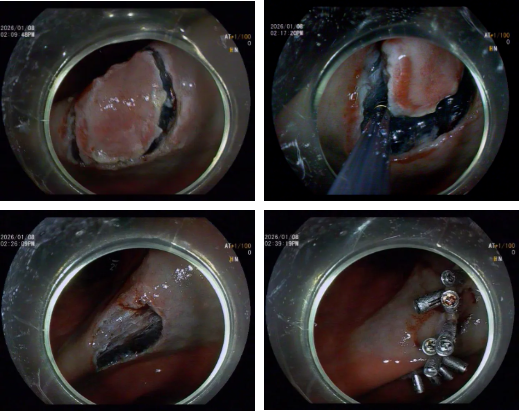

消化内科杨贵祥主治医师为其实施内镜检查中敏锐发现其胃窦表面粗糙不平坦伴有发红及糜烂,凭借多年临床经验,杨医生结合胃镜下特殊光染色,初步判断该处组织可能为恶性病变的潜在风险,立即取病理两块进行送检。同时密切与患者保持联系,病理结果回示:胃窦粘膜慢性活动性炎,伴面膜上皮和腺体高级别上皮内瘤变,局部疑小灶间质浸润。针对沈大叔的病情,消化内科吴勇主任带领团队进行充分术前论证,决定采用内镜黏膜下剥离术(ESD)进行治疗。手术由吴勇主任主刀,术中凭借精湛技巧仔细分离病灶与正常组织,最终成功完成剥离,整个手术过程未出现出血情况。

ESD 的全称是内镜黏膜下剥离术,即医生通过患者口腔或肛门,将带有高清摄像头和特殊器械的内镜伸入消化道,在病变组织下方注射药物使其抬起,再用专用刀器将病变完整剥离并取出,全程无需开腹,仅在消化道黏膜表面操作。